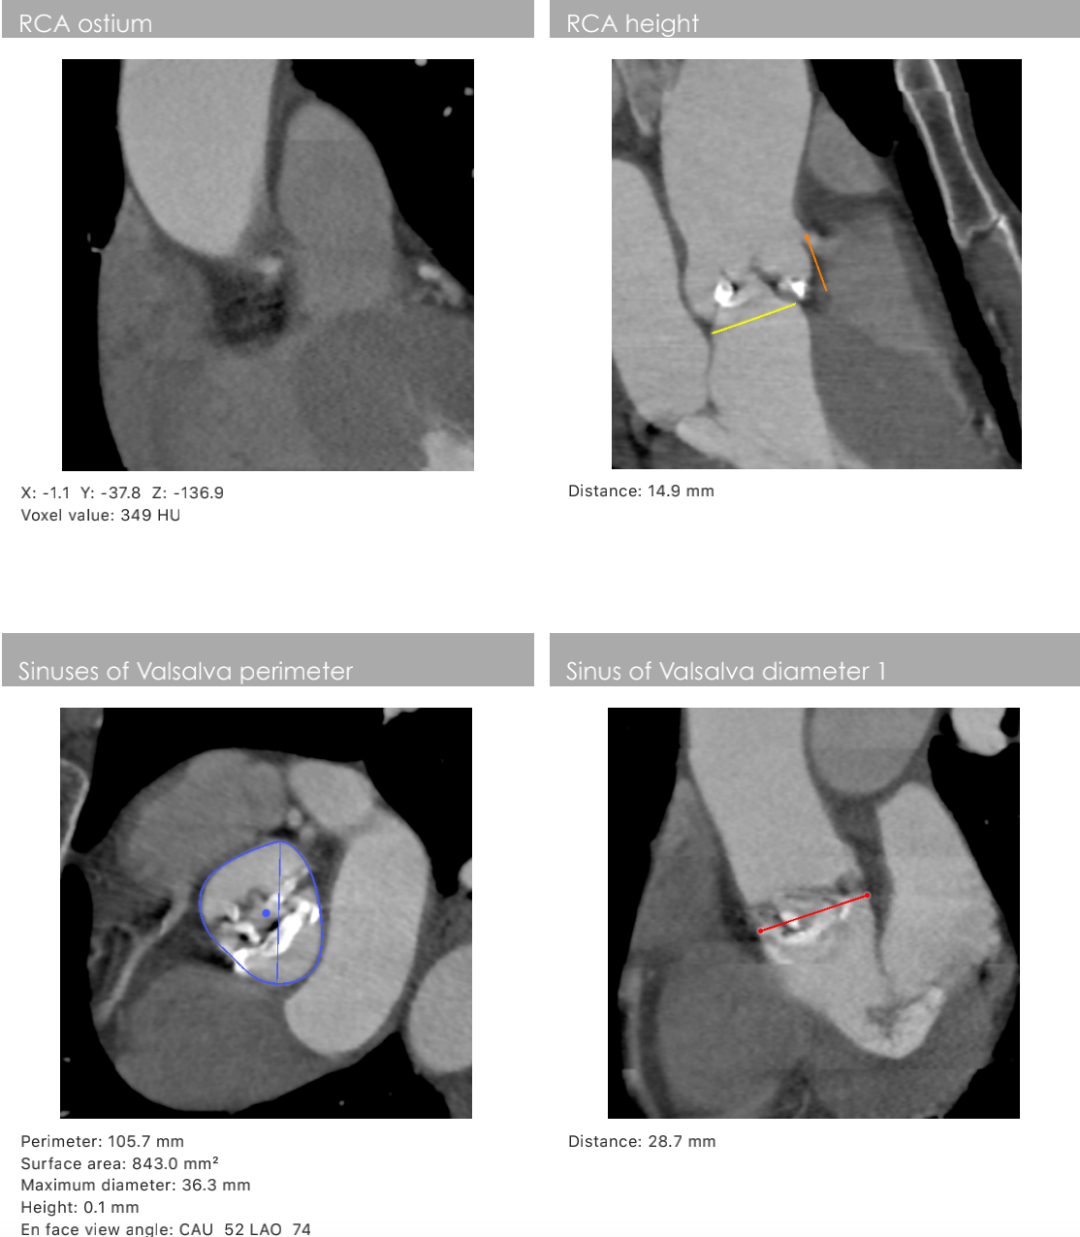

主动脉根部数据:

主动脉瓣环周长82.2mm(平均直径26.1mm),流出道周长89.6mm(平均直径28.5mm),左冠高度:15.4mm,右边冠高:14.9mm,主动脉窦宽28.7mm/33.7mm/34.9mm、STJ周长:93.5mm(平均直径29.7mm)高度22.2mm,升主动脉周长:111.7mm(平均直径35.5mm)。

术前心胸外科、心血管内科、超声科、麻醉科、体外循环、介入室等科室进行了术前讨论和术前策略分析:该患者主动脉瓣属于钙化狭窄的Type0型二叶瓣,左右冠脉同窦,无冠窦可见团状钙化,左右同窦钙化相对较少,主动脉瓣环周长82.2mm、呈现椭圆形,左室流出道周长89.6mm,主动脉窦宽28.7mm/33.7mm/34.9mm、窦宽可,STJ周长93.5mm、高度22.2mm,升主动脉周长111.7mm。患者心室壁明显增厚心尖较薄。左冠高度15.4mm右冠高度14.9mm,双冠高度可。患者右股动脉分叉点位于股骨头下缘,穿刺点内径为8.1mm,血管无明显钙化轻度迂曲。左股动脉分叉点位于股骨头下缘,穿刺点内径为7.8mm,血管无明显钙化轻度迂曲。选择右侧股动脉为主入路,左侧股动脉可作为辅入路;考虑患者主动脉瓣二叶式畸形,钙化严重,采用DOWNSIZE策略,综合评估选择20mm/22mm球囊预扩;患者瓣环周长82.2mm,考虑TAV27型号瓣膜。